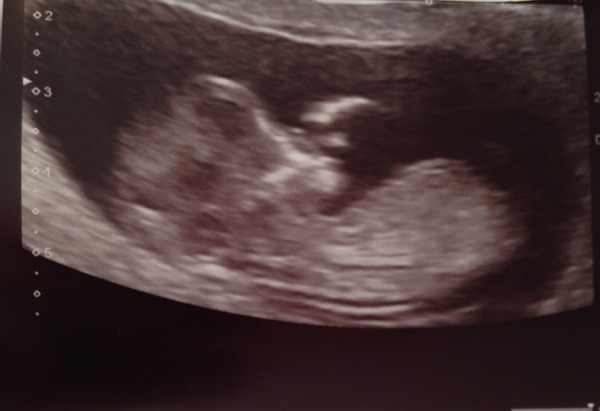

Well have just spent a good 5 minutes deleting photos off my phone to make room (there were 600 odd Blush) and... here he/she is!

This is my favourite pic because you can see his/her little hand...

bonjourminou, love it!

Love it BonjourMinou!

Great scan pic Bonjour